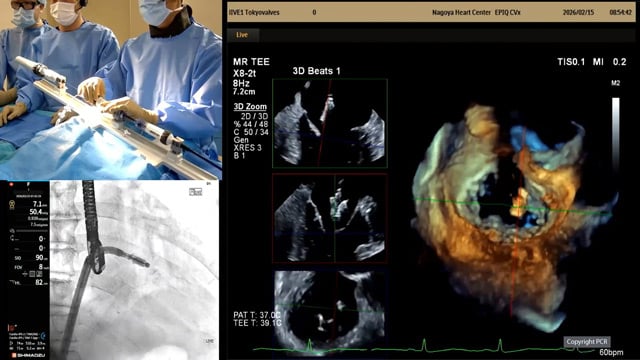

Primary mitral TEER in small anatomy - LIVE case

15 Feb 2026 – From PCR Tokyo Valves 2026

An 89-year-old male with diabetes mellitus, hypertension, chronic kidney disease (eGFR: 46), and CAD with a history of NSTEMI and CTO of the RCA, presented with symptomatic primary mitral regurgitation (P1–P2 prolapse) and preserved LV function (56%).One Pascal ACE device was implanted.